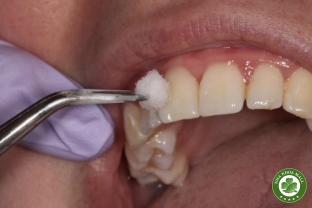

• Nha khoa thẩm mỹ: Tẩy trắng răng, dán sứ veneer, bọc răng sứ.